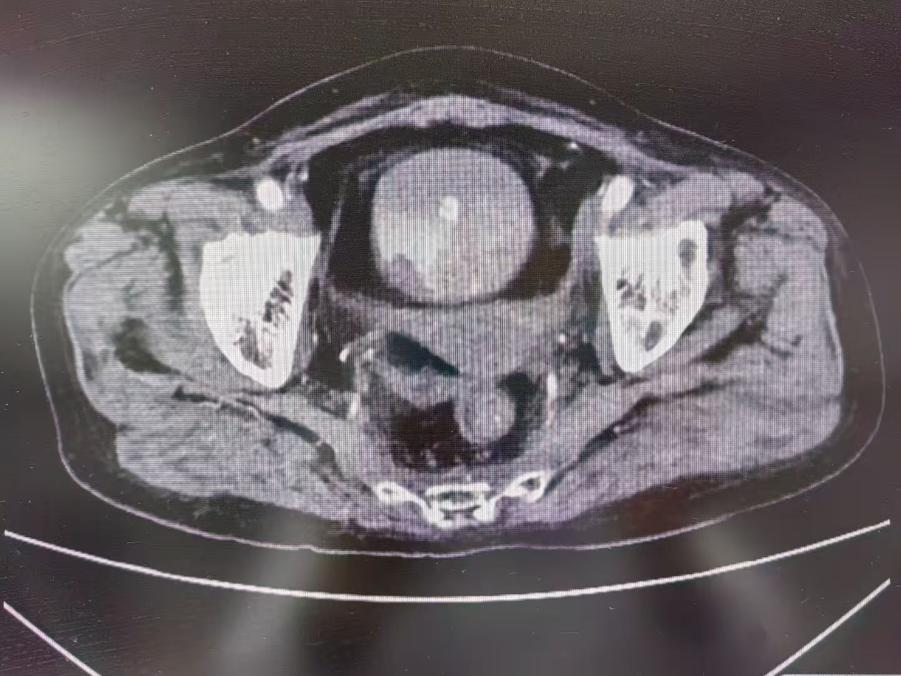

近期,我院肿瘤科及介入团队顺利为一名宫颈癌治疗后并发顽固性血尿的老年患者实施介入止血治疗,目前患者已经脱离危险顺利出院。患者为老年女性,一年前因宫颈癌行同步放化疗及后装治疗。近2个月,患者出现持续血尿,血红蛋白低至44克/升,虽经多次输血支持,血红蛋白回升仍不理想。入院后,肿瘤科迅速启动多学科评估,协同介入团队为患者实...